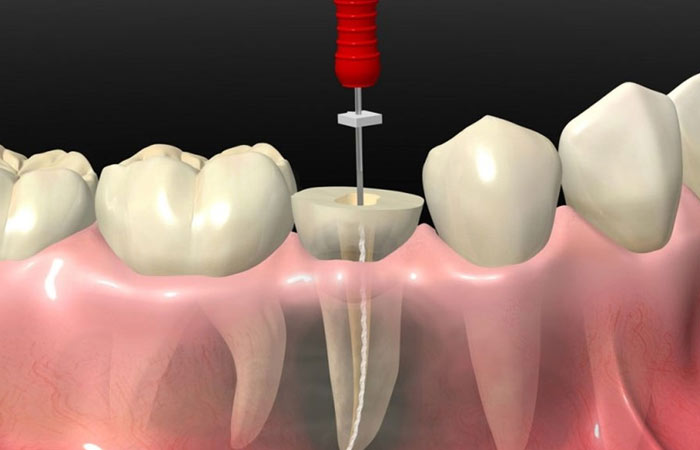

جراحی ایمپلنت: در این مرحله، ایمپلنت (پیچ تیتانیومی) در استخوان فک قرار داده میشود. این فرآیند تحت بیحسی موضعی انجام میشود.

بهبود و پیوند استخوان: پس از جراحی، چند ماه زمان لازم است تا ایمپلنت به طور کامل با استخوان فک جوش بخورد (عملیه اوستیونتگراسیون).